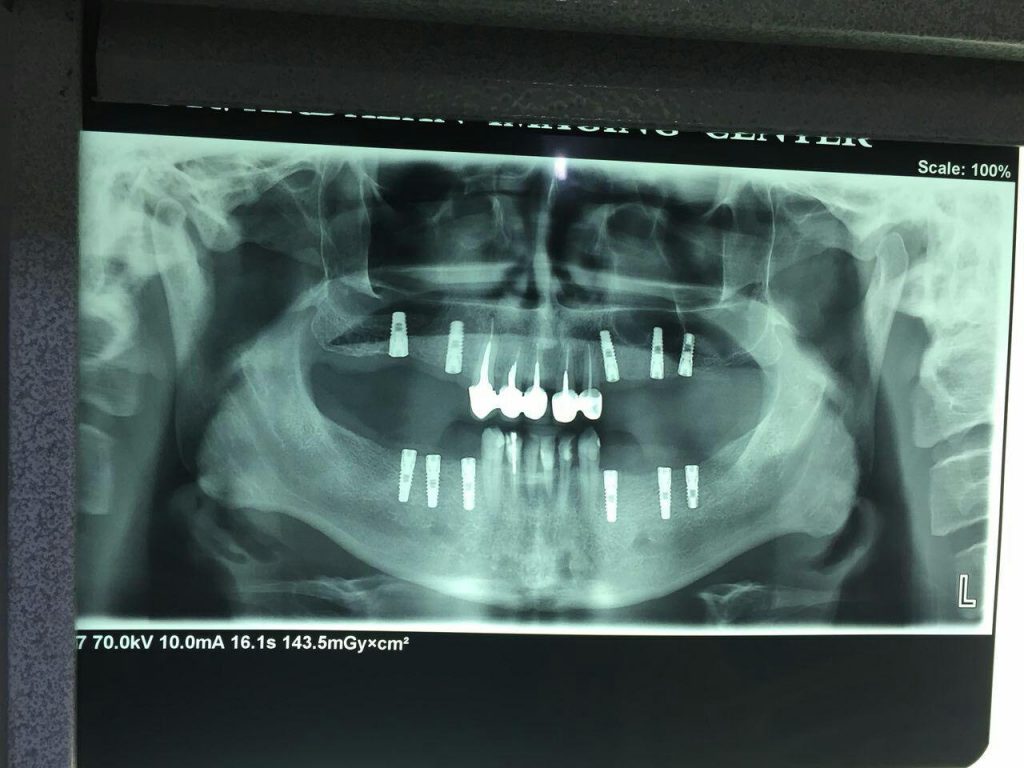

– جراحی های پیشرفته ایمپلنت دندان

جراحی ایمپلنت دندان و گذاشتن پروتز در ناحیه فک و صورت